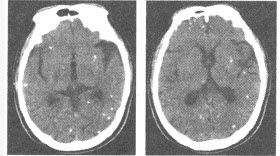

A:各年龄段均可发病,好发于长骨干骺端

C:CT及MRI上可见液-液平面

D:病灶主要由大小不等海绵状血池组成,分为原发性和继发性两种

E:是肿瘤样病变,而非真正意义上的肿瘤